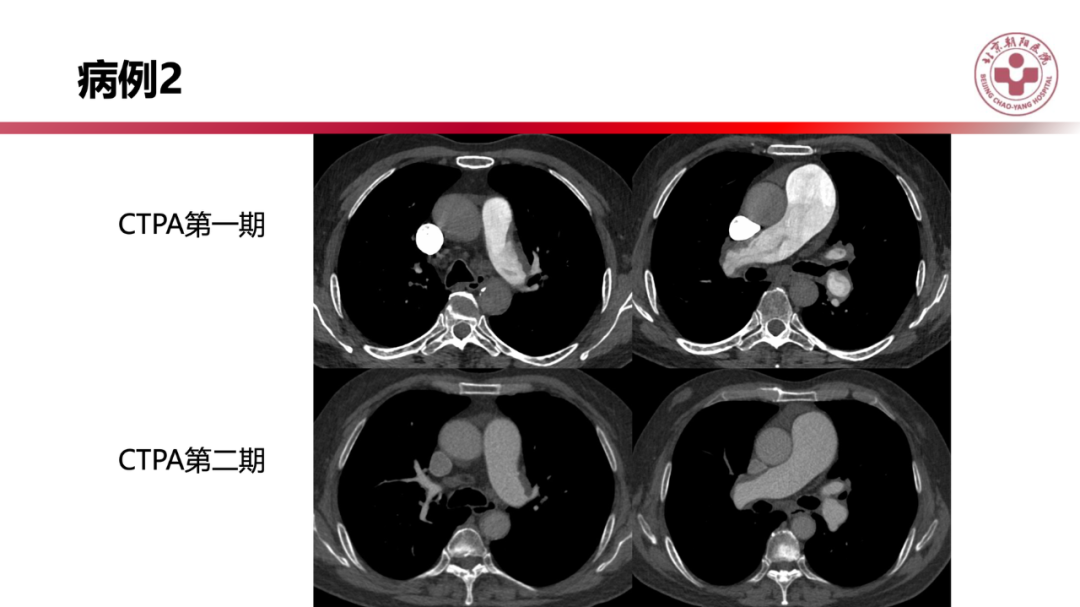

肺栓塞后,肺动脉高压如何治疗?

来源 北京朝阳医院放射介入影像中心